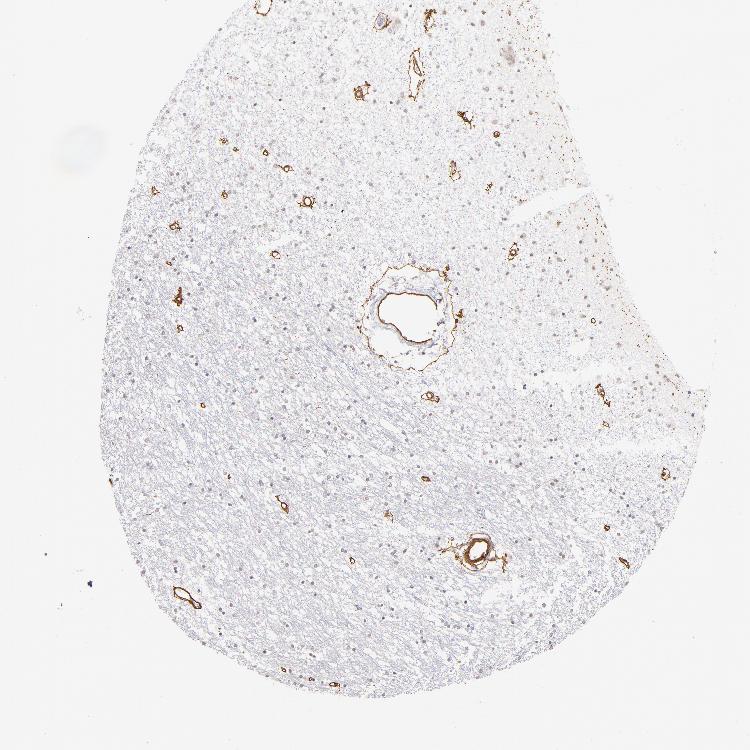

CAUDATE - Antibody stainingi

Antibody staining in the annotated cell types in the current human tissue is reported as not detected, low, medium, or high, based on conventional immunohistochemistry profiling in selected tissues. This score is based on the combination of the staining intensity and fraction of stained cells.

Each image is clickable and will lead to virtual microscopy that enables deeper exploration of all samples and also displays staining intensity scores, fraction scores and subcellular localization as well as patient and tissue information for each sample.

Antibody HPA001908Antibody HPA001909Antibody CAB004486Antibody CAB078163

Glial cells Not detectedNot detectedNot detectedNot detected

Neuronal cells -LowNot detectedNot detected